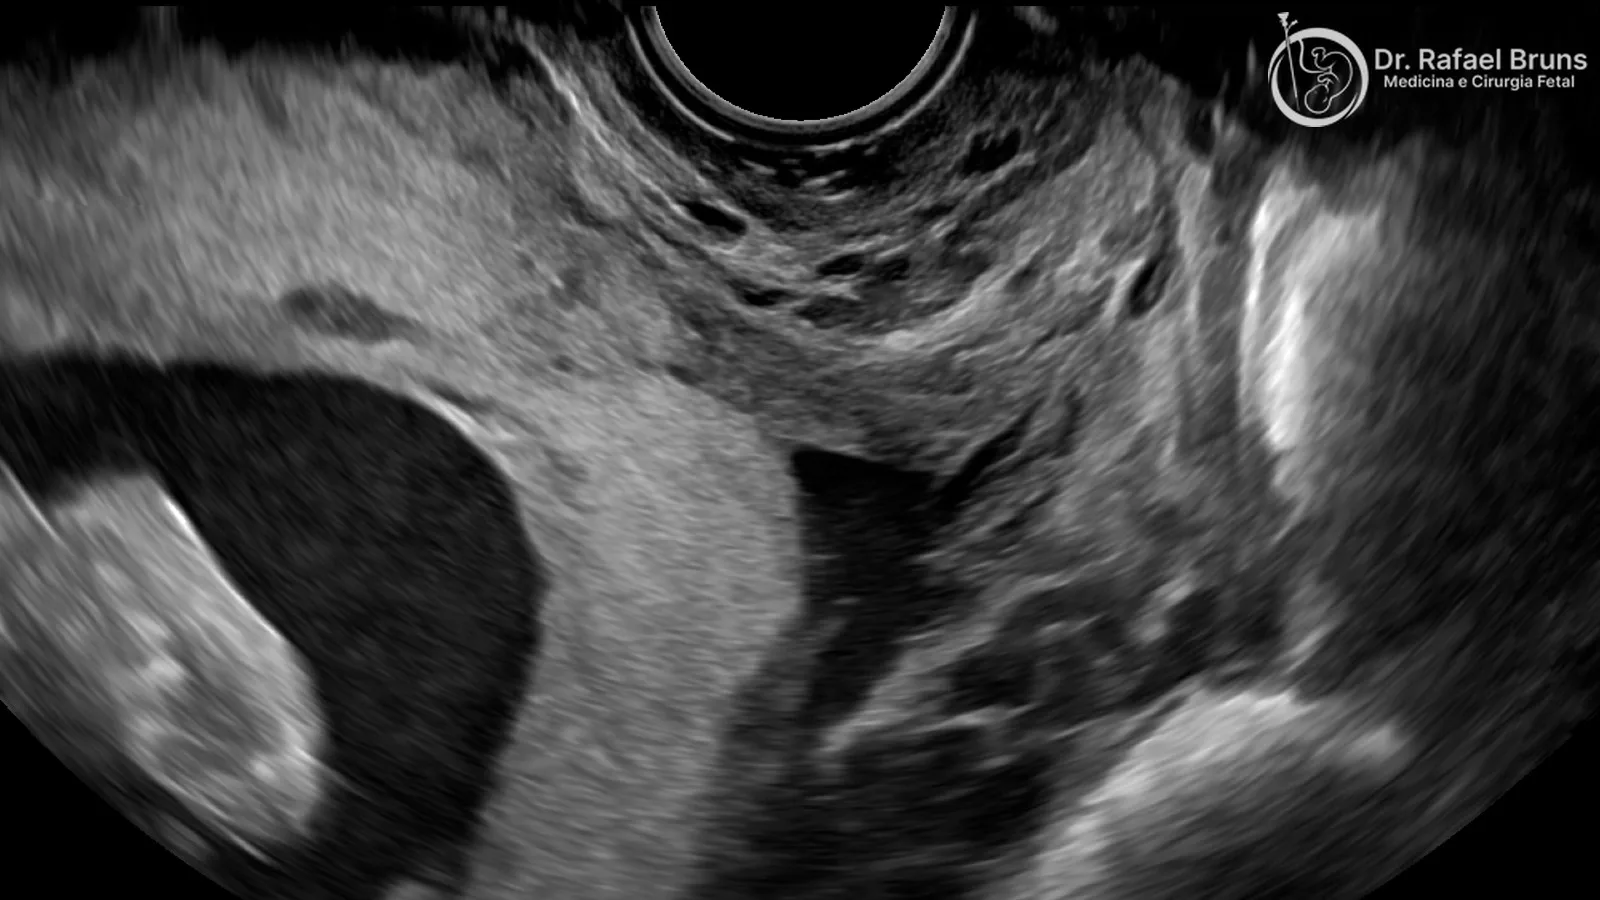

Ultrassom transvaginal: o exame de referência

Quando há suspeita de placenta prévia, o ultrassom transvaginal mede com exatidão a distância entre a borda placentária e o orifício interno do colo. A sonda transvaginal permite visualizar o segmento inferior sem a interferência do tecido adiposo ou da posição fetal. É seguro: a via transvaginal não alcança o colo uterino e estudos controlados não mostram aumento de sangramento associado ao exame.